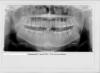

После приема у ортодонта получил такое заключение по прикусу - глубокая резцовая окклюзия

Фото ОПТГ прилагаю, ТРГ в боковой проекции пока не сделал

8-ки все давно вылезли, что по словам врача и привело к смещению челюстей. Челюсть "рыхлая" и что удивительно я совсем не чувствовал боли при прорезывании мудростей))

Врач предлагает удалить все 8-ки, ибо места для движения зубов нет и установить брекеты на обе челюсти